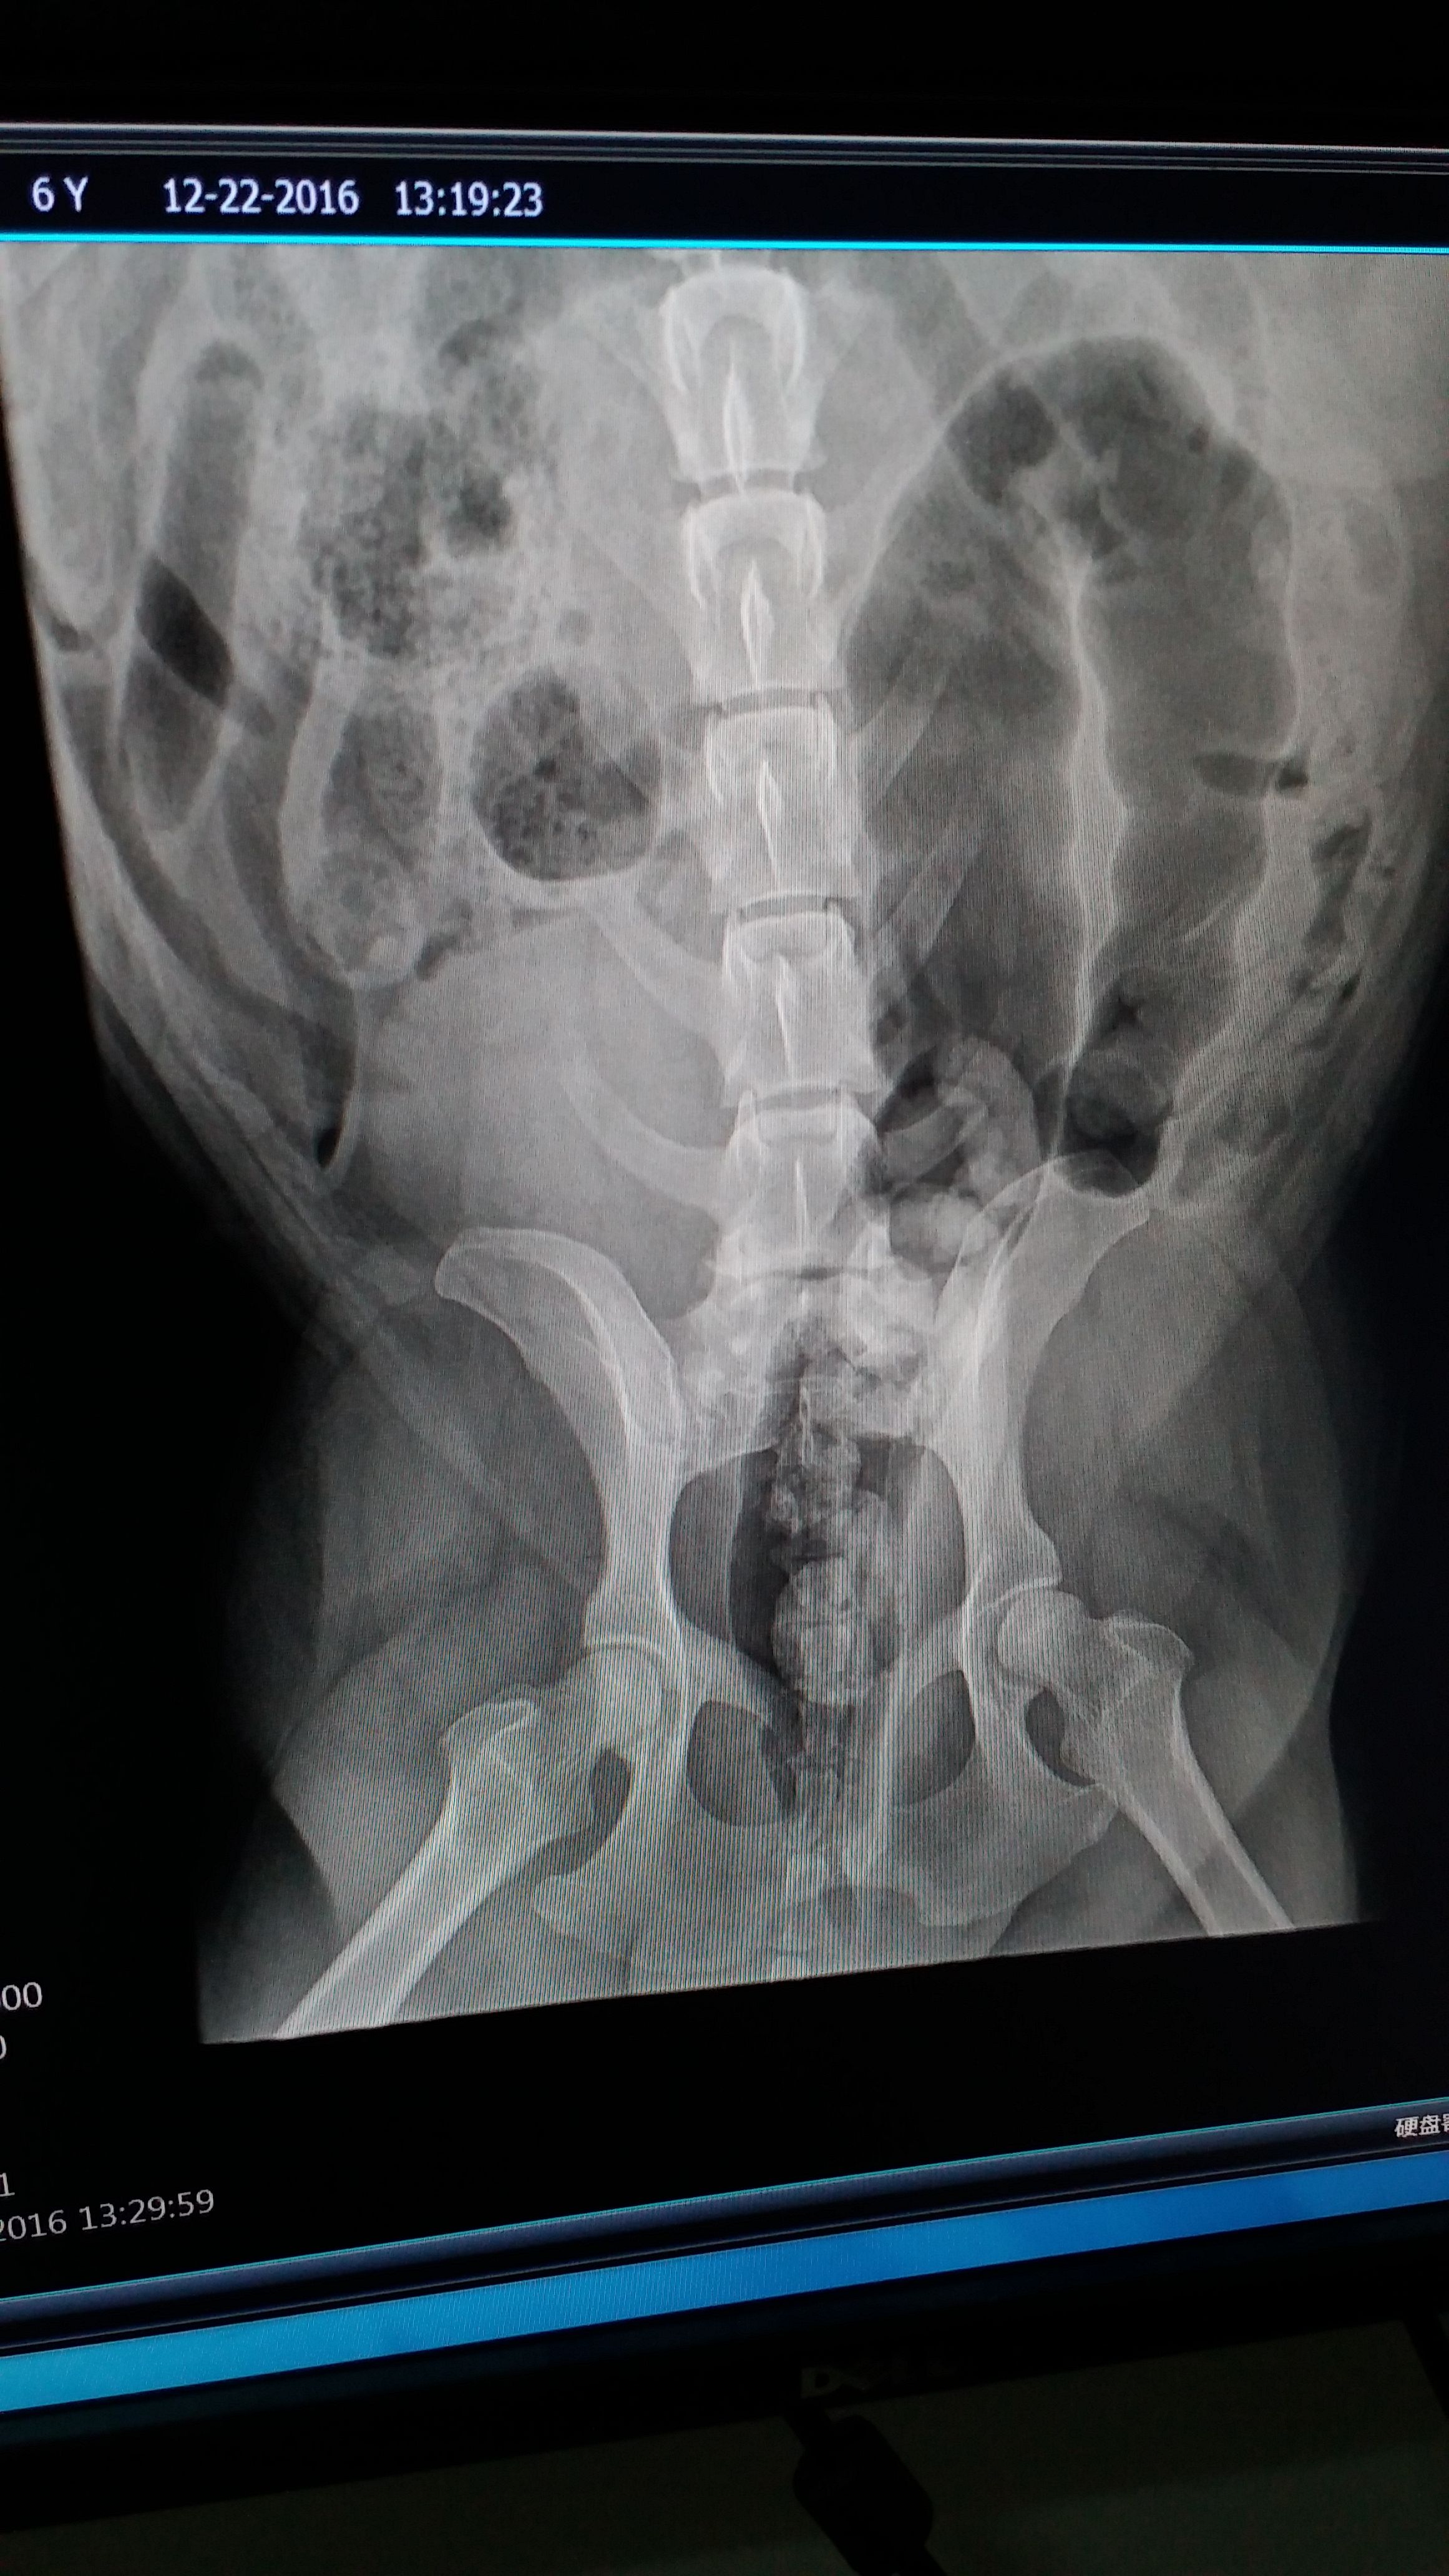

金毛犬,六岁,体重九十斤,拍片后发现患有关节炎及髋关节内有骨质增生,不愿意走路,不愿意上下楼梯,夜晚疼痛一夜不能入睡,不停的折腾。医生建议减肥,并服用三七片每天八粒,另外给它搭配了卫仕关节舒及小宠关节康一起使用,效果不大,吧里哪位朋友有好的办法希望推荐一下,毕竟狗狗才六岁,这样下去非常糟心。

髋关节没问题,现在是关节炎+骨质增生,大夫确实让减肥到75斤,现在它自己也不怎么吃东西,问题是运动量也跟着下降,近二十天了,我估计最多瘦了两斤。

我家的狗不是髋关节的问题,拍了片子髋关节没事,但是现在是关节炎外加体重超标,大夫让减肥到75斤,可它饿呀,我实在是看不得它无辜的小眼神。愁死我了。